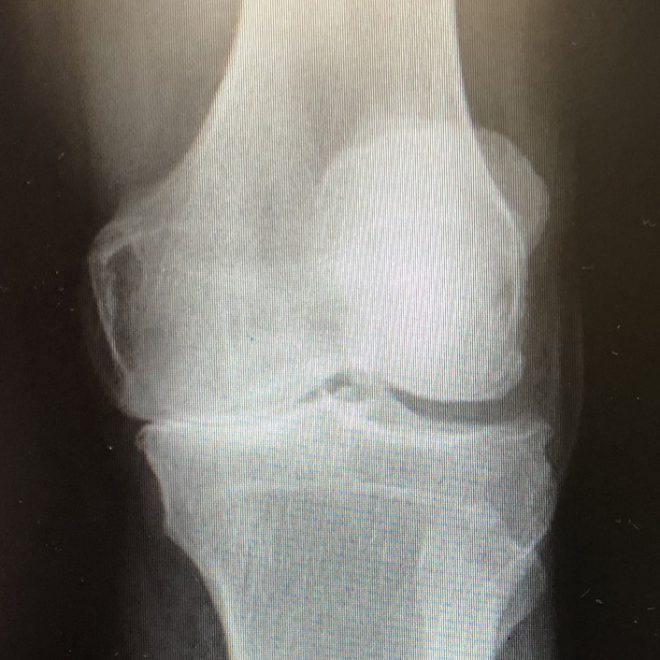

Si se utilizan elementos clínicos complementados con una radiografía basta con que ésta presente osteofítos, es decir que presente crecimiento excesivo de tejido óseo alrededor o dentro de la articulación en cuestión y que se presente al menos uno de los criterios siguientes:

Para reconocer una artrosis de rodilla gracias a una radiografía, se tiene que observar un espacio articular reducido y la presencia de osteofitos.[3]

De acuerdo a la escala de Kellgren y Lawrence se puede estudiar la progresión de la artrosis, estableciendo así distintos grados según diferentes criterios como lo son la presencia de osteofitos, los cambios en el hueso subcondral, entre otros.